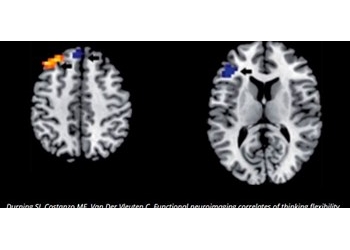

El pensamiento analítico y no analítico activa patrones anatómicos funcionales distintos

La "teoría dual del razonamiento" ha recibido un sólido sustento biológico en una investigación publicada en la Revista Medical Teacher, entre cuyos autores está el Dr. Cees P.M. van der Vleuten, miembro del Comité Científico de la Fundación Practicum.

Novatos y expertos clínicos activan áreas hemisféricas distintas en la toma de decisiones

A medida que los clínicos progresan, todo indica que la toma de decisiones descansa menos en el saber biomédico de base y más en la experiencia previa. Y, de acuerdo con un estudio publicado en Advances in Health Sciences Education, conforme aumenta la dificultad, el proceso de decisión clínica activa áreas neuronales distintas.